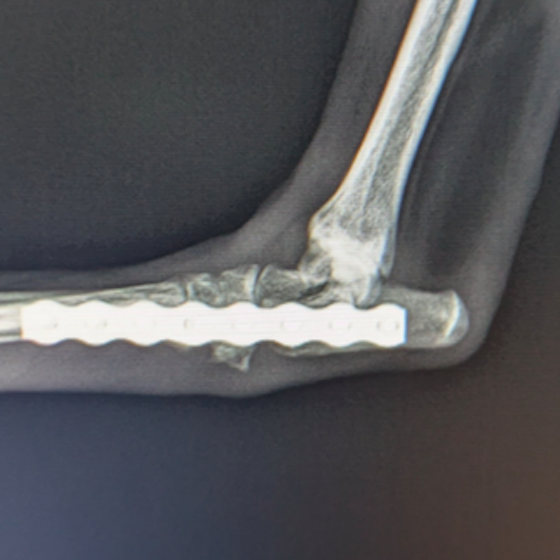

症例:柴犬 3歳

左後肢の完全挙上を主訴に来院されました。触診にて近位足根関節の過伸展を、レントゲン検査にて左足根関節周囲の軟部組織の腫脹、ストレス撮影によって距骨・踵骨と第4足根骨・中心足根骨間の脱臼および過伸展を認めました。

術中において、浅趾屈筋腱を剥離、内方へ牽引し、直接踵骨から第4足根骨までピンを挿入し(あらかじめ細いピンで下穴をあけておくとよい)、テンションバンドワイヤー法を併用し、関節軟骨の掻爬と海綿骨移植を実施しました。

術後レントゲン画像上に癒合が認められるまで約2ヵ月間は、運動を制限する必要があります。

術前正面像左関節の腫れ

左足根関節の軟部組織が腫脹しています。

術前正面像

術前側面像屈曲位

術前側面像伸展位